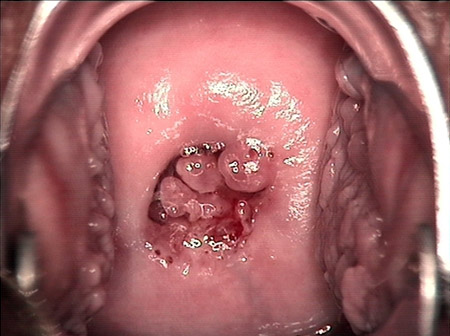

婦科leep錐切手術(shù) CIN2-3

• CIN 2-3CIN 2-3

• CIN 2-3 碘著色后CIN 2-3 碘著色后

• CIN 2-3 leep術(shù)后CIN 2-3 leep術(shù)后

• CIN 2-3 修復(fù)后CIN 2-3 修復(fù)后

• CIN 2-3 修復(fù)后(圖2)CIN 2-3 修復(fù)后(圖2)